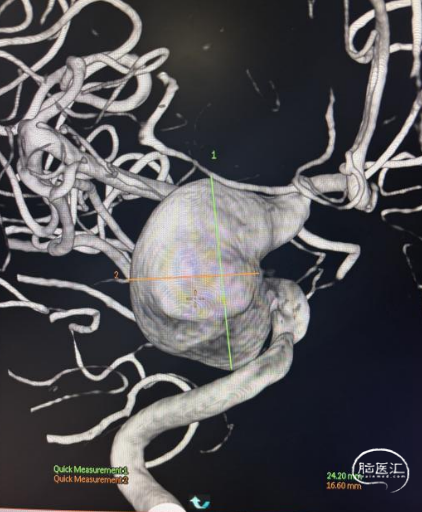

术前影像

脑动脉DSA提示右侧颈内动脉虹吸段巨大动脉瘤。

右侧虹吸段载瘤动脉近端直径为4.13mm,瘤体最宽径为24.2mm,动脉瘤流入、流出道均显示明显迂曲,近端载瘤动脉也有迂曲。病变范围约32mm。